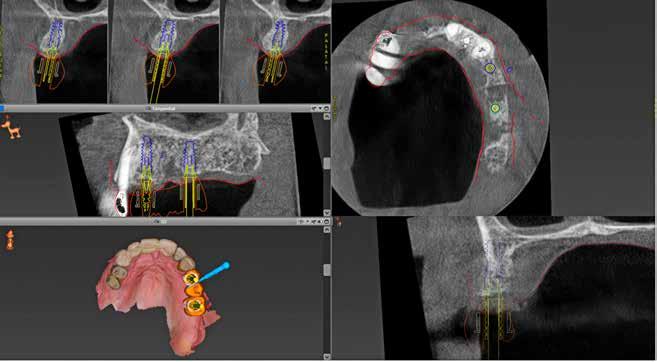

REZAI E, PERSSON M, NØRHOLT SE Statisk computerassisteret implantatkirurgi / 578

I den tredje artikel, som er en oversigtsartikel, vender vi os mod computerassisteret implantatkirurgi. Vi har igennem de senere år løbende bragt artikler om mange forskellige aspekter af implantatkirurgi. Denne artikels fokus er statisk computerassisteret implantatkirurgi, der indebærer anvendelse af en guideskinne, der støtter borets retning og dybde, således at den virtuelt planlagte implantatposition overføres til patienten. Metoden er anvendelig, hvor implantater indsættes tæt på vigtige anatomiske strukturer eller i den æstetiske zone. Artiklen diskuterer fordele og begrænsninger ved

anvendelse af metoden sammenlignet med eksempelvis frihåndsimplantatkirurgi.